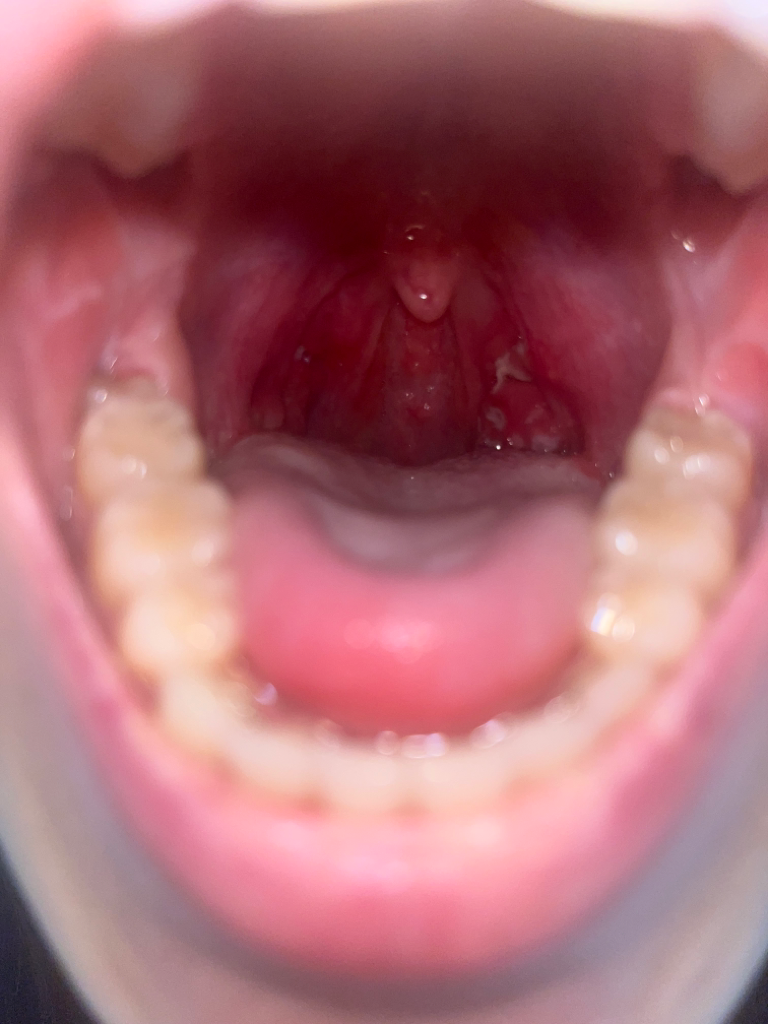

^^ 암이 그리 잘 생기는 것은 아니랍니다. 편도염 재발이 잦은 것이 암을 의미하지는 않구요. 일단 염증 치료 잘 받으시고 치료에도 불구하고 증상이 좋아지지 않는다면 암의 가능성도 고려해야 하나 사진으로는 가능성은 매우 낮을 것으로 생각됩니다. 편도염이 불편하시다면 제거 수술을 고려하시면 됩니다.

암으로 보이는 병변은 보이지 않습니다. 재발성 편도염이 있다면 암이 발생할 수 있으나 그 가능성이 높지는 않습니다.

현재 편도염이 있는 상황으로 보이며 그밖의 다른 정보를 얻기엔 제한적입니다. 또한 편도염이 편도암으로 이어지지는 않습니다. 그러니 너무 걱정마시고 치료 잘 받으시기 바랍니다.

사진상으로는 편도부종외 특이할만한 소견이 관찰되는 것으로 보이지는 않습니다. 급성편도염이 호전되고 난뒤에도 목에 이물감이나 불편감이 지속된다면 이비인후과 진료를 받아 보시기 바랍니다.